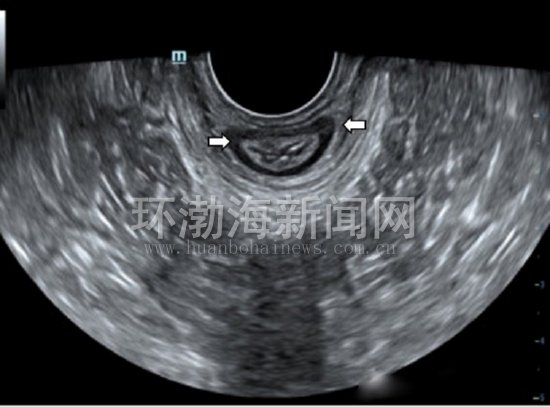

患者,张女士,30岁,阴道分娩1次,产后7个月,因咳嗽、大笑、打喷嚏时漏尿,产后便秘等症状到该院就诊。经该院盆底超声检查发现,在完成最大乏式动作(Valsalva)时膀胱内口呈锥形扩张,直肠前壁向后膨出;肛门内外括约肌完整,静息状态时肛提肌裂孔的三维图像呈规则的菱形,前、中及后三腔室结构完整紧凑,最大乏式动作时肛提肌裂孔面积稍有增大,但结构仍然完整紧凑。这样,一下子找到了过去不算病的“病根”,到相关科室对症治疗及解决了多日的“尴尬”。

图3:肛门内外括约肌二维图像